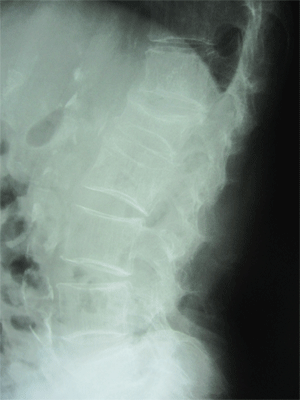

• 圧迫骨折

圧迫骨折は上下方向の力と前屈によって起こり骨粗しょう症の方はクシャミや腰を捻った、尻もちをついたなどの日常動作でも容易に圧迫骨折することがあります。

好発部位は胸から腰にかけての所(第11胸椎~第2腰痛の胸腰椎移行部)です。